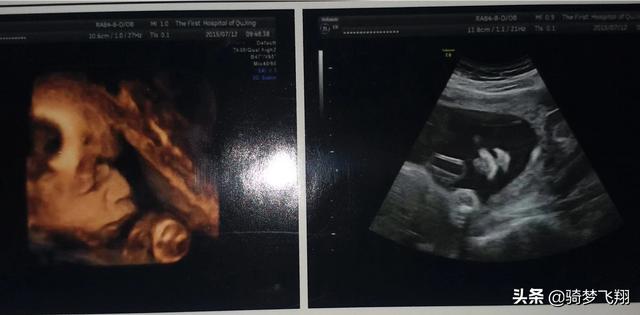

不同产前检查最佳时间需根据检查内容而定,四维彩超的最佳时间一般在26-28周。

四维彩超正常我是两次,一次24周,一次30周,本来应该32周做的,但是约的时候就约的30周的时间。但是第二次四维也做了两次,第一次也是宝宝不配合医生说有的地方没看到,爬了楼梯在做的。医生也比较粗鲁扶着肚子一直摇,让宝宝变换姿势,不过还好我没有什么不舒服的地方。

一般我们这里正常孕检是五十天确认宫内孕有无胎心,12-14周做NT,16-18周唐筛或者无创,24-26第一次四维加糖耐,这个是在一天做的。30-32周第二次四维。基本大检查就没有了,后面就是半个月一次胎心监护。37周以后一个礼拜一次!